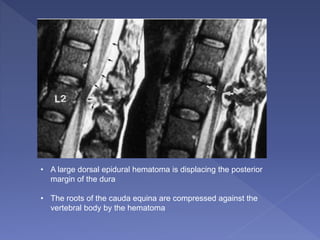

• A large dorsal epidural hematoma is displacing the posterior

margin of the dura

• The roots of the cauda equina are compressed against the

vertebral body by the hematoma